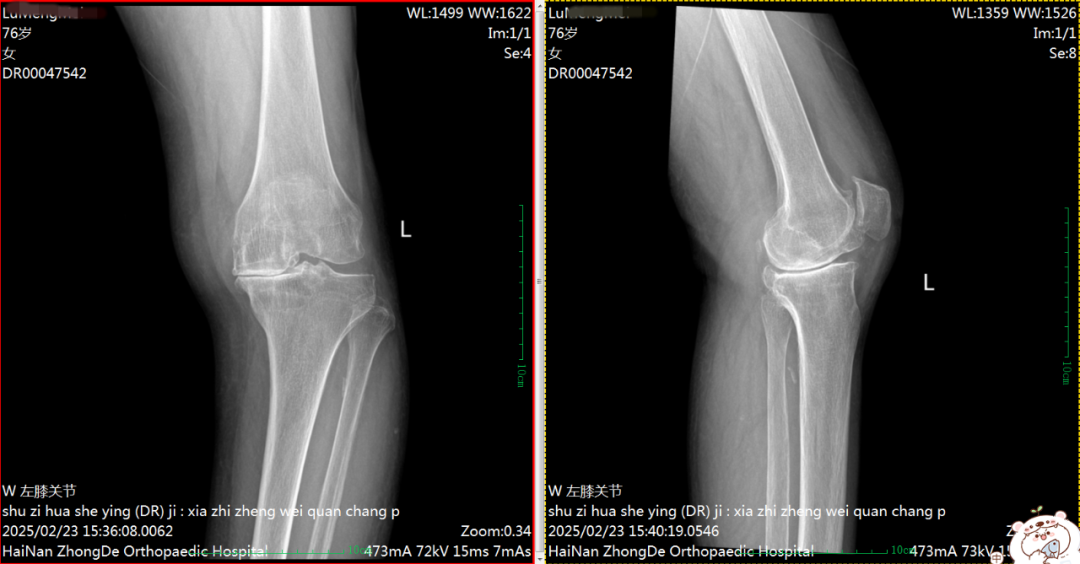

术前DR片